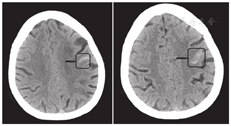

患者女性,74岁,因"发作性言语不利伴口角歪斜4 h"于2018年4月10日入院。患者于入院前无明显诱因出现吐字含糊不清,伴右侧口角歪斜,持续约3~5 min后自行缓解,症状间断发作,不伴头痛、头晕,无肢体活动障碍、意识障碍及大小便障碍等。门诊头颅CT(图1)示左侧额叶部分脑沟内高密度影,考虑少量SAH。以"TIA和SAH"收入院。

影像学检查:入院次日复查头颅CT示左侧额叶部分脑沟内高密度影,考虑少量SAH,较前变化不大。头颅MRI示左侧基底节区、左侧丘脑、左侧枕叶、双侧小脑半球可见多发小灶样T1低信号和T2高信号影,边界清晰(图2);弥散加权成像未见异常高信号影;双侧侧脑室周围可见轮缘状液体衰减反转恢复序列(fluid-attenuated inversion recovery, FLAIR)高信号,双额叶白质区可见多发小点片状FLAIR高信号影,边界不清;磁敏感加权成像可见左侧额部一粗大血管影,其内见高信号影(图3),另见左侧基底节区和双侧小脑半球多发小圆形低信号影;磁共振血管造影示颅内血管多发性狭窄,右侧大脑后动脉显影浅淡,远端分支减少(图4)。数字减影血管造影示左侧大脑中动脉M1段闭塞,右侧大脑后动脉P1段闭塞,左侧颈内动脉C5段轻度狭窄,右侧颈内动脉多处中至重度狭窄,双侧大脑前动脉多处狭窄,右侧大脑中动脉多处狭窄,双侧椎动脉多处狭窄,基底动脉中段多处狭窄,左侧大脑后动脉多处狭窄,未见静脉窦异常。